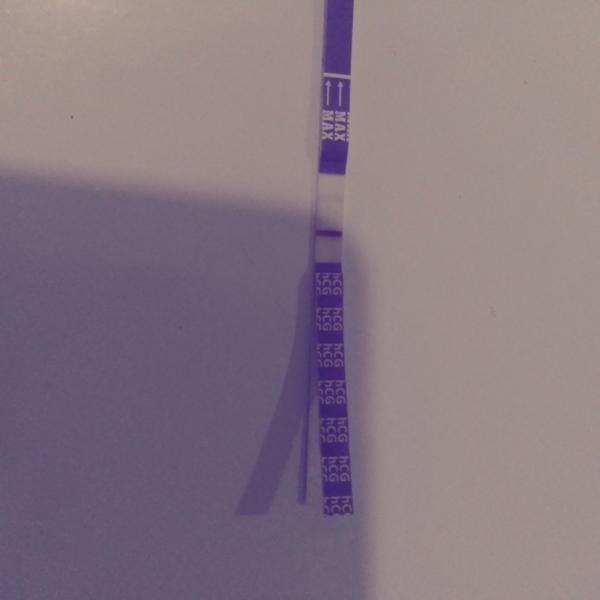

bola som u svojho gynekológa a spravil mi ultrazvuk. Vraj si nie je istý, či som tehotná, alebo mám zrazeninu. V krvi mám negatívny výsledok, ale test mi stále ukazuje pozitívny výsledok. Testy sú robené od 22.10 každý tretí deň.

Posledný piaty test bol robený 2.11.2019.